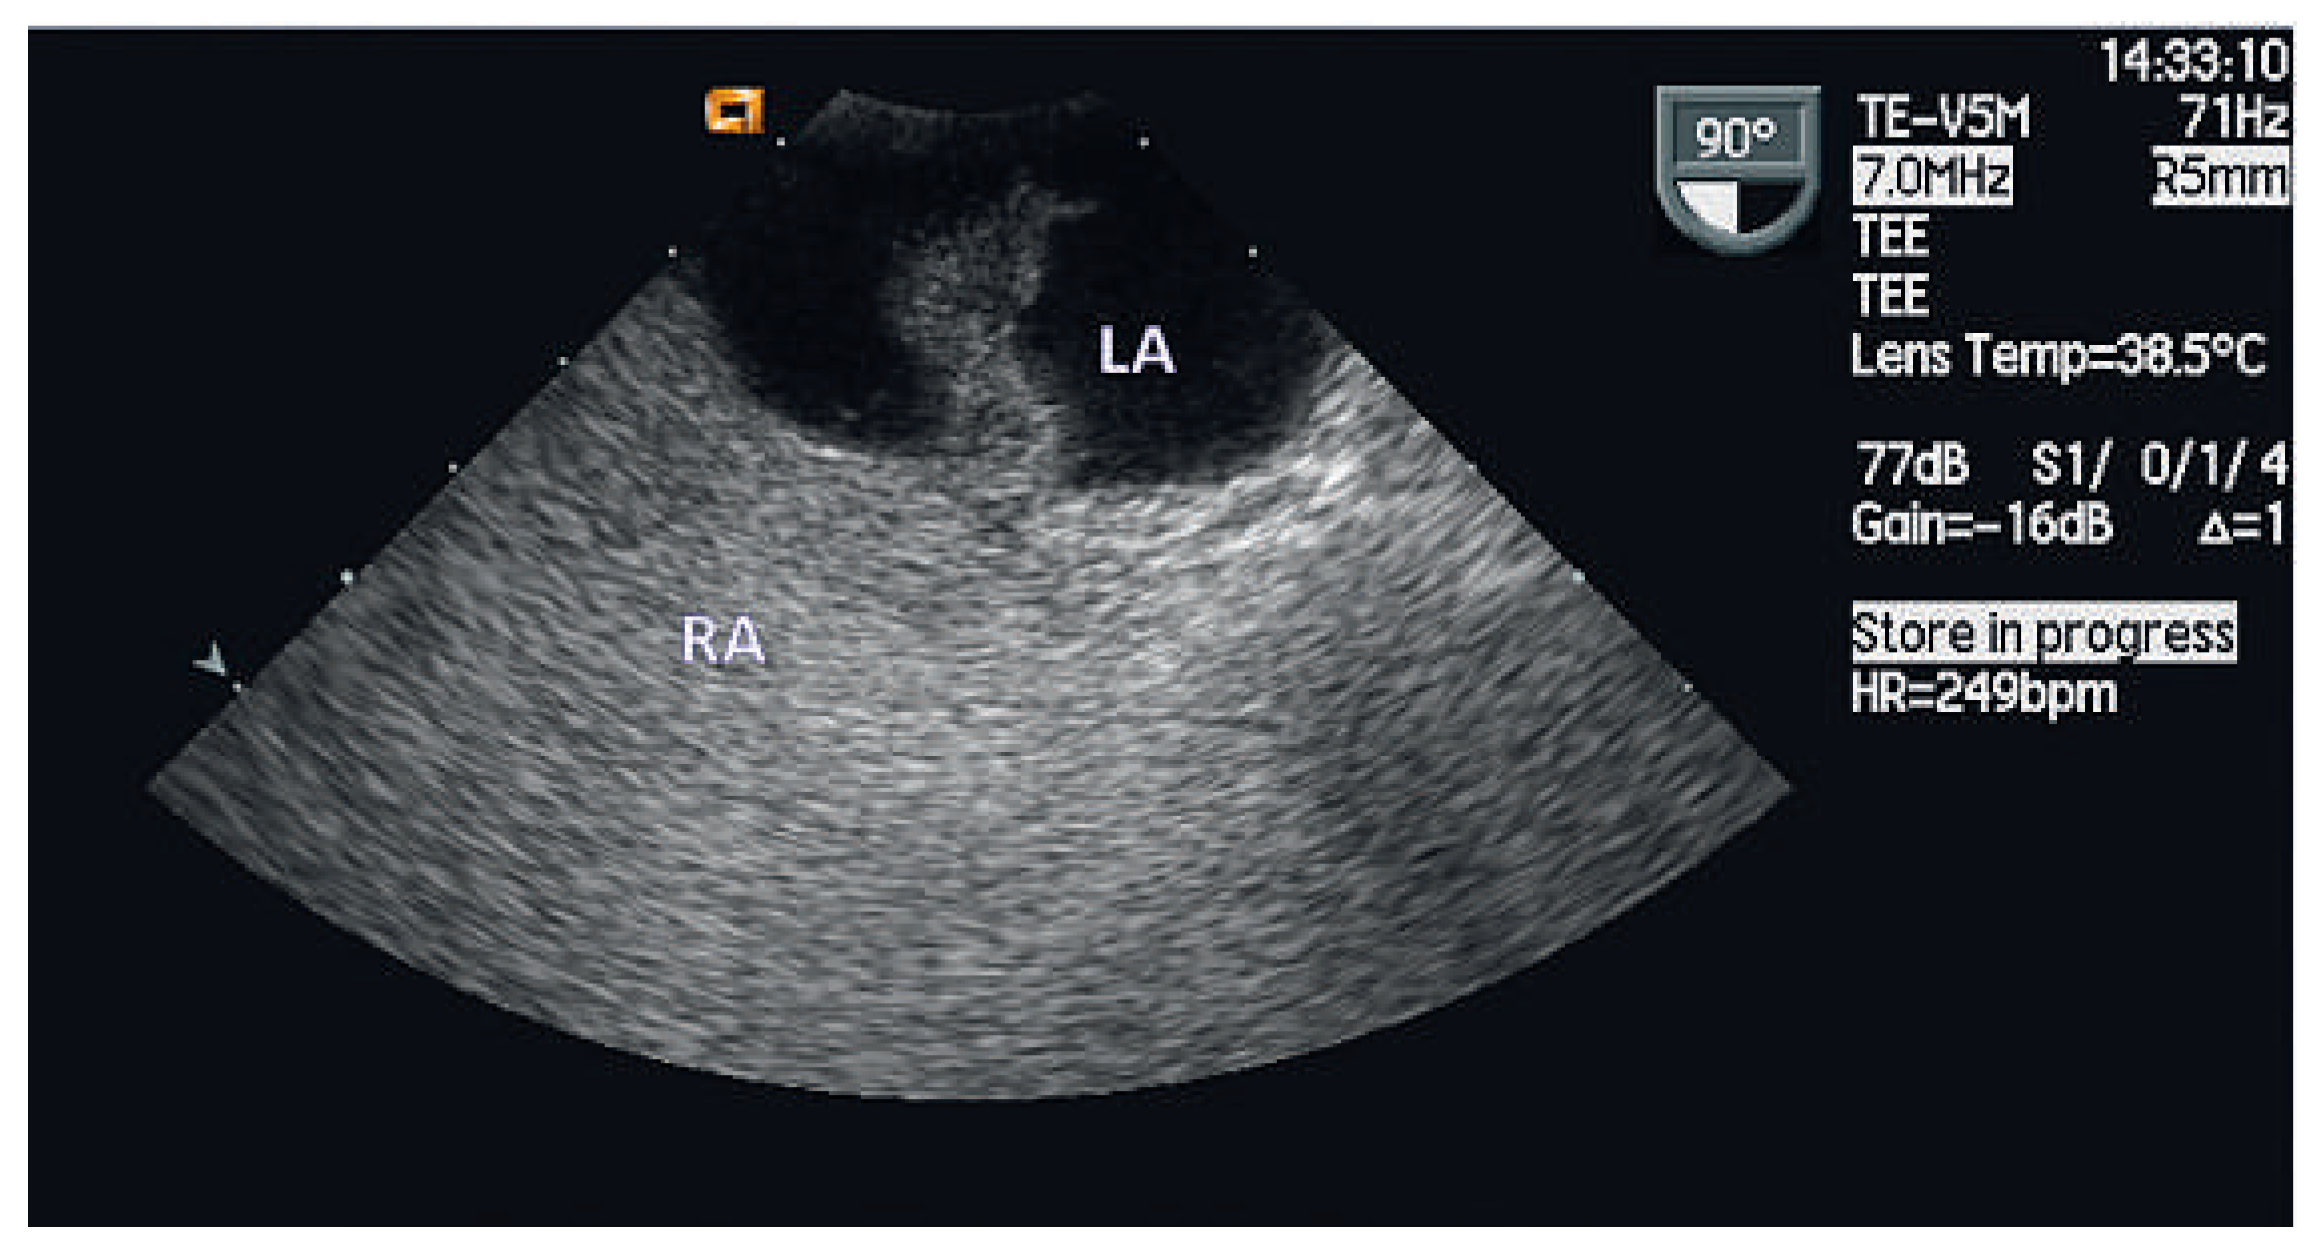

Case report